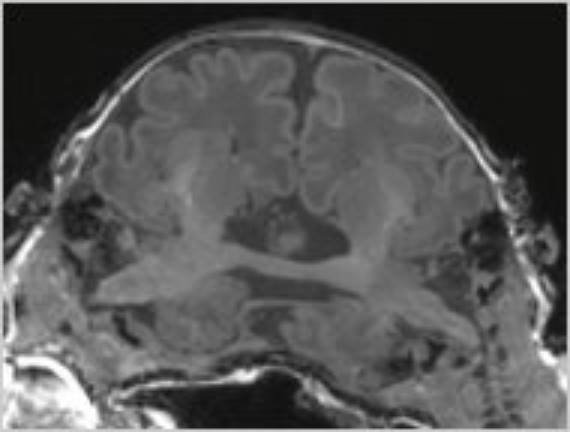

Перед вами — уникальное МРТ сразу двух человек. Это МРТ Кристы и Татьяны Хогарт. Они — краниопаги, сросшиеся черепами сиамские близнецы. Но их случай — совсем особый случай.

Дело в том, что они срослись еще и таламусами: на МРТ отчетливо виден нейронный мост между этими глубинными областями мозга сестёр. Сейчас девочкам 10 лет, однако интеллект их оценивается на 5-6. Однако удивительно другое: одна девочка может делиться напрямую через мозг ощущениями с другой. Если одна девочка, которая любит кетчуп, попробует его, другая, не любящая, скривится. Одна сестра с закрытыми глазами может видеть то, что видит вторая. Этот уникальный случай в истории нейронаук ещё ждёт подробного исследования, однако врачи не спешат, боясь травмировать психику девочек.